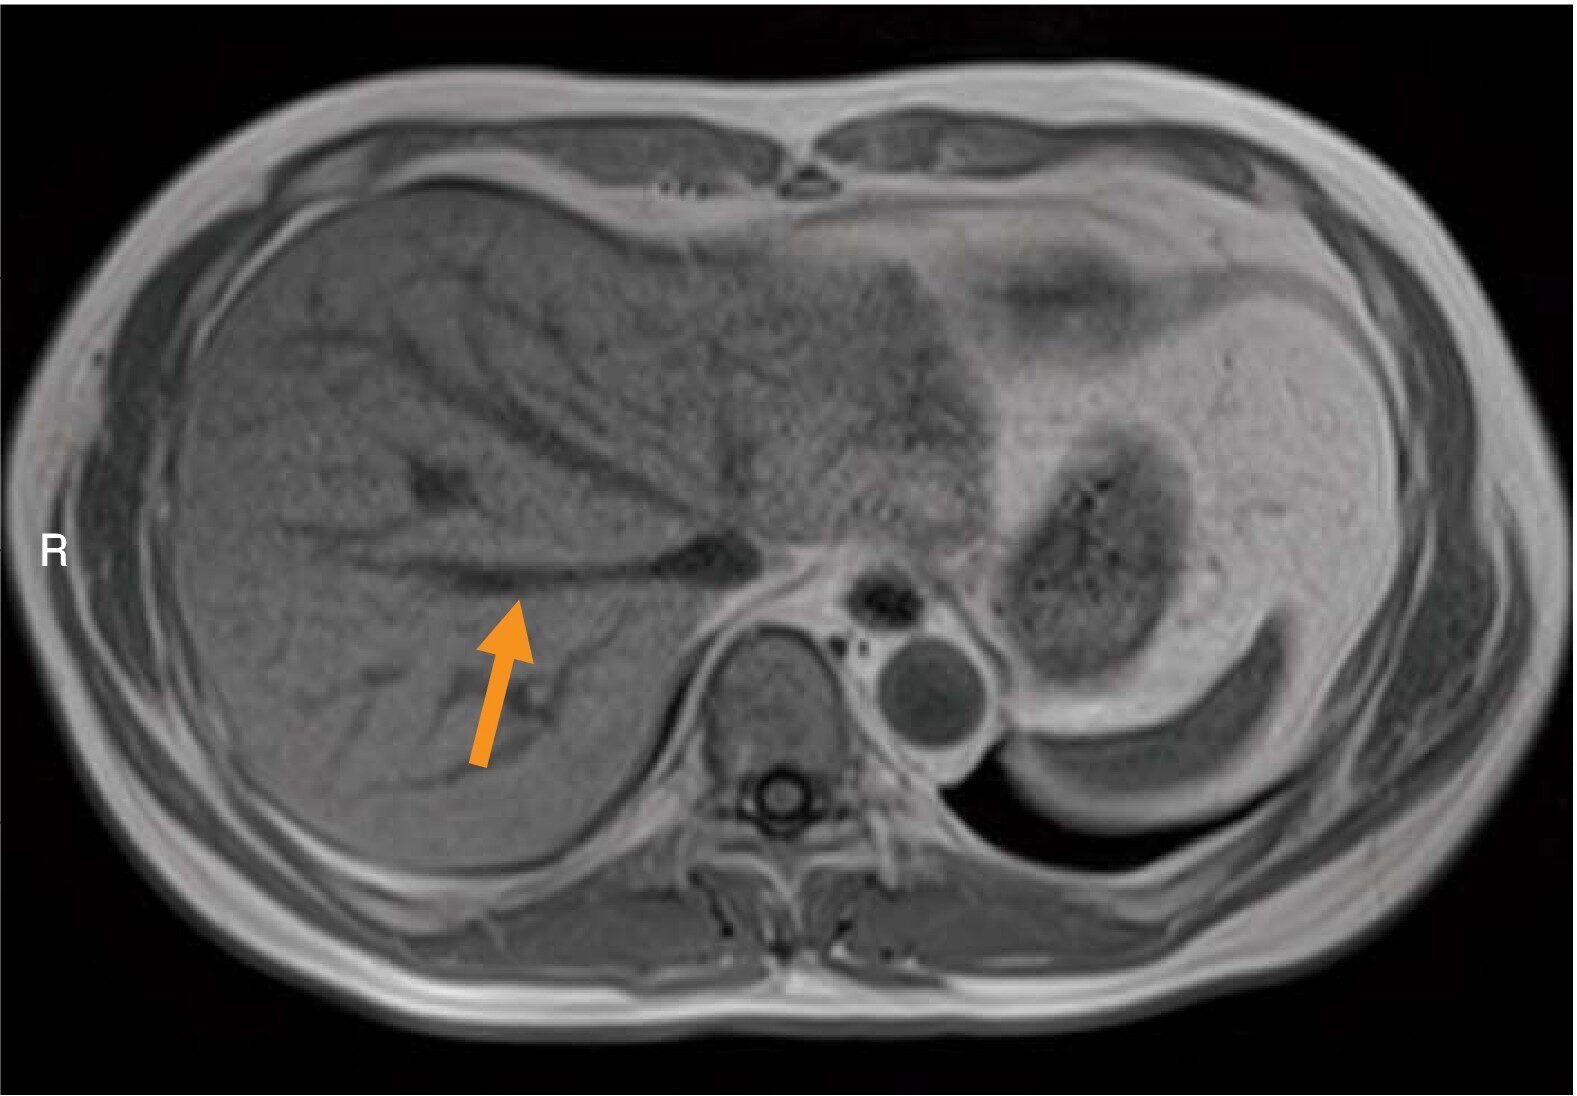

胸部MR像(別冊No.4)を別に示す。矢印で示す血管と直接交通しているのはどれか。

- 1右心房

- 2右心室

- 3左心房

- 4左心室

- 5下大静脈